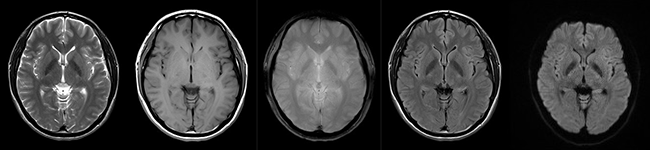

・撮像条件を変えることで、いろいろなコントラストの画像を撮像できます。

頭部の断面像 いろいろなコントラストの画像